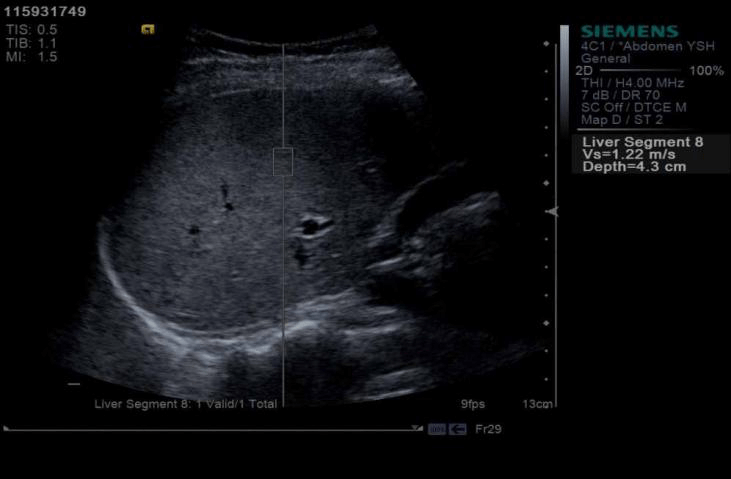

Shear wave or acoustic radiation force impulse (ARFI) from the transducer propagates in the tissue. Measurement of the propagation speed helps quantify the tissue stiffness in kilopascals or meters per second. Most important clinical use: quantitative assessment of liver stiffness. Multiple values are obtained over the right lobe of the liver and the median value is used as the index of stiffness.

Stiffer the liver, higher the recorded shear wave velocity. It is also applied in stiffness quantification in focal lesions and holds promise in stiffness imaging of spleen, kidneys and musculoskeletal system. Clinical indication for Liver Elastography:

- Evaluation of patients with unexplained portal hypertension (Normal liver stiffness in EHPVO, NCPF). Fibrosis cutoff values for US elastographic techniques are manufacturer dependent with normal values of stiffness being below 3 m/ s or 6-7 kpa and cutoff values for Cirrhosis ranging above 2.2 m/s or 15 kpa

Normal liver stiffness in a young male patient with portal hypertension. Elastography helped rule out cirrhosis